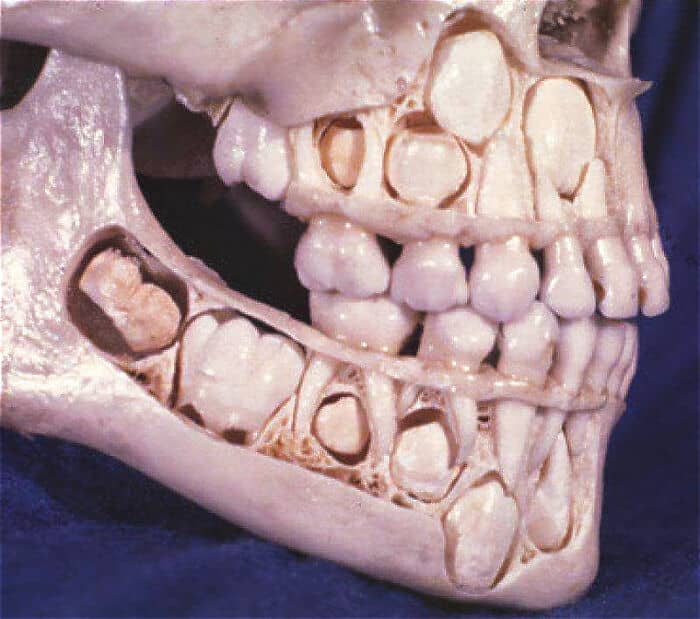

#6

A child’s jaw is literally ‘filled’ with teeth: both baby and permanent teeth are there at the same time, hidden under the gums. If you imagine this visually, it looks quite creepy.